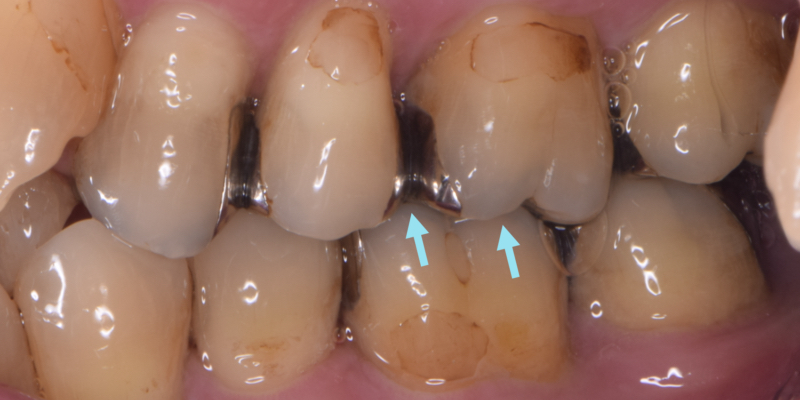

欠けていたところは咬み合わせると、矢印のように噛み込んで強く力がかかる部分です。

この部位に銀歯の境界線を作ると、将来、冒頭の写真のように欠けるため、それを避けるデザインにする必要があります。

長持ちするには、そのような本来行うべき「理想の治療」があります。

欠けた理由は、それを正しく行わなかったから、です。

誤解を恐れず言えば、予定通り欠けた、ということです。